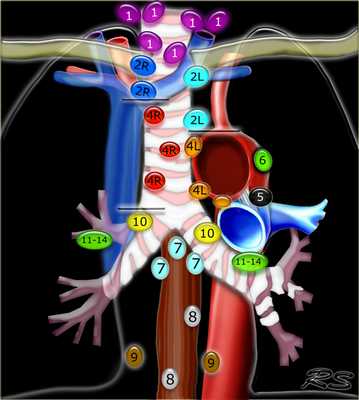

Современная классификация Американского объединенного комитета по изучению злокачественных опухолей и Американской академии оториноларингологии и хирургии головы и шеи изменена K. Robbins с соавт. в 2000 г. и утверждена AJCC-AAOHNS в 2001 г. В ней предложено разделить 3 уровня на подуровни. Классификация лимфатических узлов по уровням известна во всем мире, удобна в использовании, легка для запоминания и, что самое главное, позволяет специалистам говорить на одном языке. Она уже стала основой для классификации шейных диссекций.

I (IA и IB) - ниже тела нижней челюсти (позади ветви нижней челюсти - это уже IIA);

IA — группа подбородочных узлов

IB — группа подчелюстных лимфатических узлов (находятся спереди и сзади от подчелюстной слюнной железы). При поражении лимфатических узлов этого уровня или самой железы, то она удаляется.

II, III, IV - яремные - вдоль сосудисто-нервного пучка (внутренней яремной вены) прикрыты m.sternoclaidomastoideus

II - верхние яремные - от уровня основания черепа до уровня нижнего края подъязычной кости

IIA — верхние яремные передние — кпереди от заднего края внутренней яремной вены;

IIB — верхние яремные задние — кзади от заднего края внутренней яремной вены.

III — средние яремные - от уровня нижнего края подъязычной кости до уровня нижнего края перстневидного хряща гортани;

IV - нижние яремные — от уровня нижнего края перстневидного хряща гортани до ключиц (в т.ч. Вирховские);

V - заднего (латерального) треугольника шеи соответствует анатомическим границам

VA - акцессорные - выше уровня нижнего края перстневидного хряща, по передней поверхности трапецевидной мышцы,

VB - надключичные — ниже уровня нижнего края перстневидного хряща (исключая Вирховские);

VI - переднего пространства шеи — пре- и паратрахеальные ЛУ, предгортанные (Delphian (Дельфийские) и околощитовидные ЛУ, включающие ЛУ вдоль возвратного гортанного нерва)

Группы лимфатических узлов не входящих в классификацию.

При описании всех перечисленных ниже групп лимфатических узлов необходимо использовать традиционные названия.

1. Лимфатические узлы заушной области.

2. Подзатылочные лимфатические узлы.

3. Околоушные лимфатические узлы (внутри и внеоколоушной слюнной железы).

4. Латеральные и медиальные ретрофарингеальные лимфатические узлы (их поражение имеет значение при раке носоглотки и ротоглотки).

5. Лицевые лимфатические узлы.

6. Верхние медиастинальные лимфатические узлы (не относятся к лимфатическим узлам шеи).